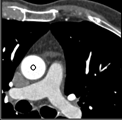

Samples for ascending aorta detection (black circle):

Cluster of candidate points in the ascending aorta.